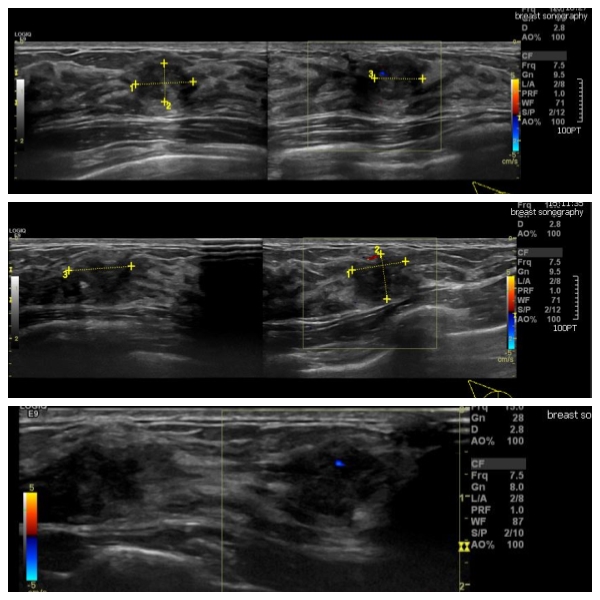

상기환자 우측 유방에 만져지는 몽우리로 내원하신 30대 여성으로 우측 7시 방향에 만져지는 몽우리와 7시 방향에서 3cm 떨어진 거리의 몽우리 조직검사 시행하였고, 침윤성

유방암 진단 되었습니다.